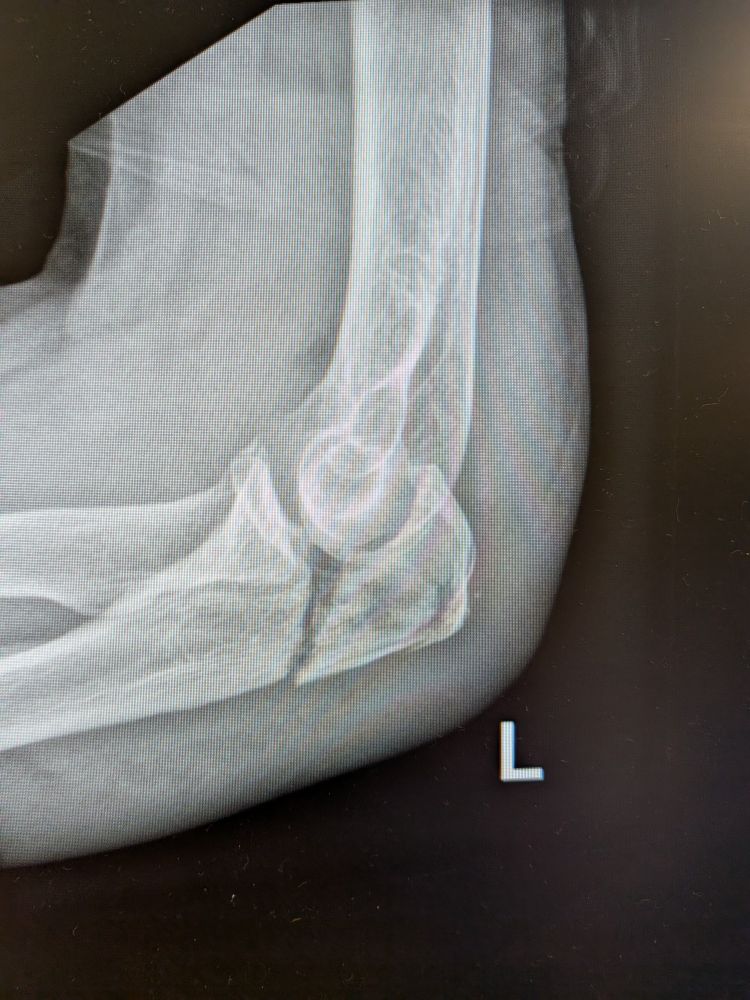

How would you describe and treat this fracture ?

#ortho #orthosky #orthopedics #emergemcy #medaky #emedsky